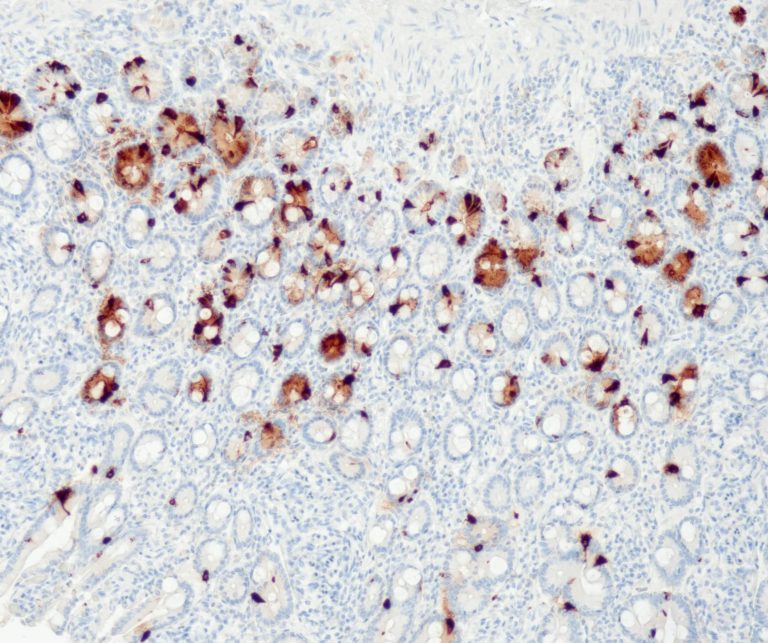

Gastrointestinal (GI) Pathology